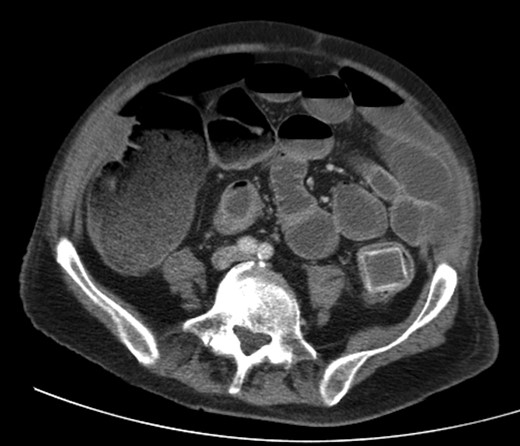

A 92-year male, with no significant co-morbidities apart from peptic ulcers, was admitted with 6 days of obstination. On examination he was dehydrated, with a hugely distended abdomen but no signs of peritonitis. Blood showed features of dehydration and plain abdominal X-ray demonstrated both small and large bowel dilatation, but no obvious causal pathology. A contrast-enhanced computed tomography scan revealed a 2.5-cm partially calcified gallstone impacted at the descending colon-sigmoid junction (Fig. 1). There was no stricture or diverticular disease distal to the stone. A cholecysto-colic fistula could be seen (Fig. 2), with a further smaller gallstone in the caecum (Fig. 3). The offending gallstone could be seen incidentally in the gallbladder on imaging 3 years previously (Fig. 4).

The offending gallstone as an incidental finding 3 years previously.